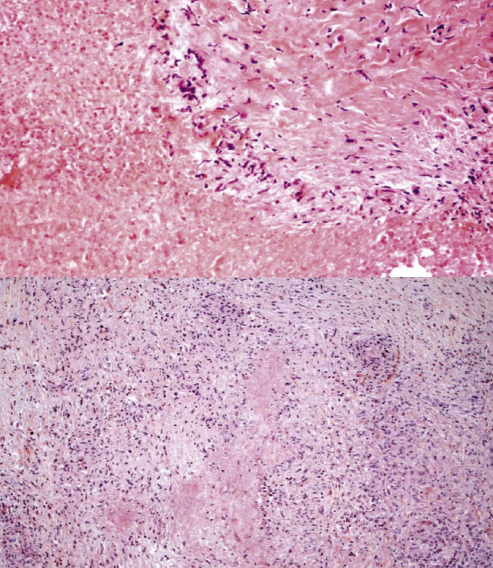

神秘的黄色肉芽肿_尹磊医生文章_海军军医大学第三附属医院(东方肝胆

图片尺寸720x462